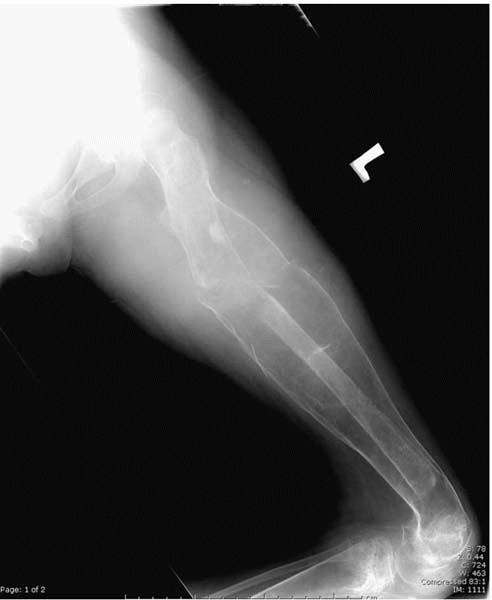

▪ FIGURE 15-2

Radiograph of a femur of a nonambulator with cerebral palsy who has sustained multiple femur fractures. The clinical and radiographic appearance of this fracture may be confused with infection. |

ambulation are at an increased risk for osteopenic fractures. In an

insensate area, fractures are often not appreciated at the time of

injury, and present late as a swollen, red, and warm limb that is often

mistaken for infection by the inexperienced. To make things even more

confusing, the child may present with a fever and abnormal laboratory

studies. This scenario unfortunately occurs in children who have severe

communication challenges (Figs. 15-2, 15-3 and 15-4).